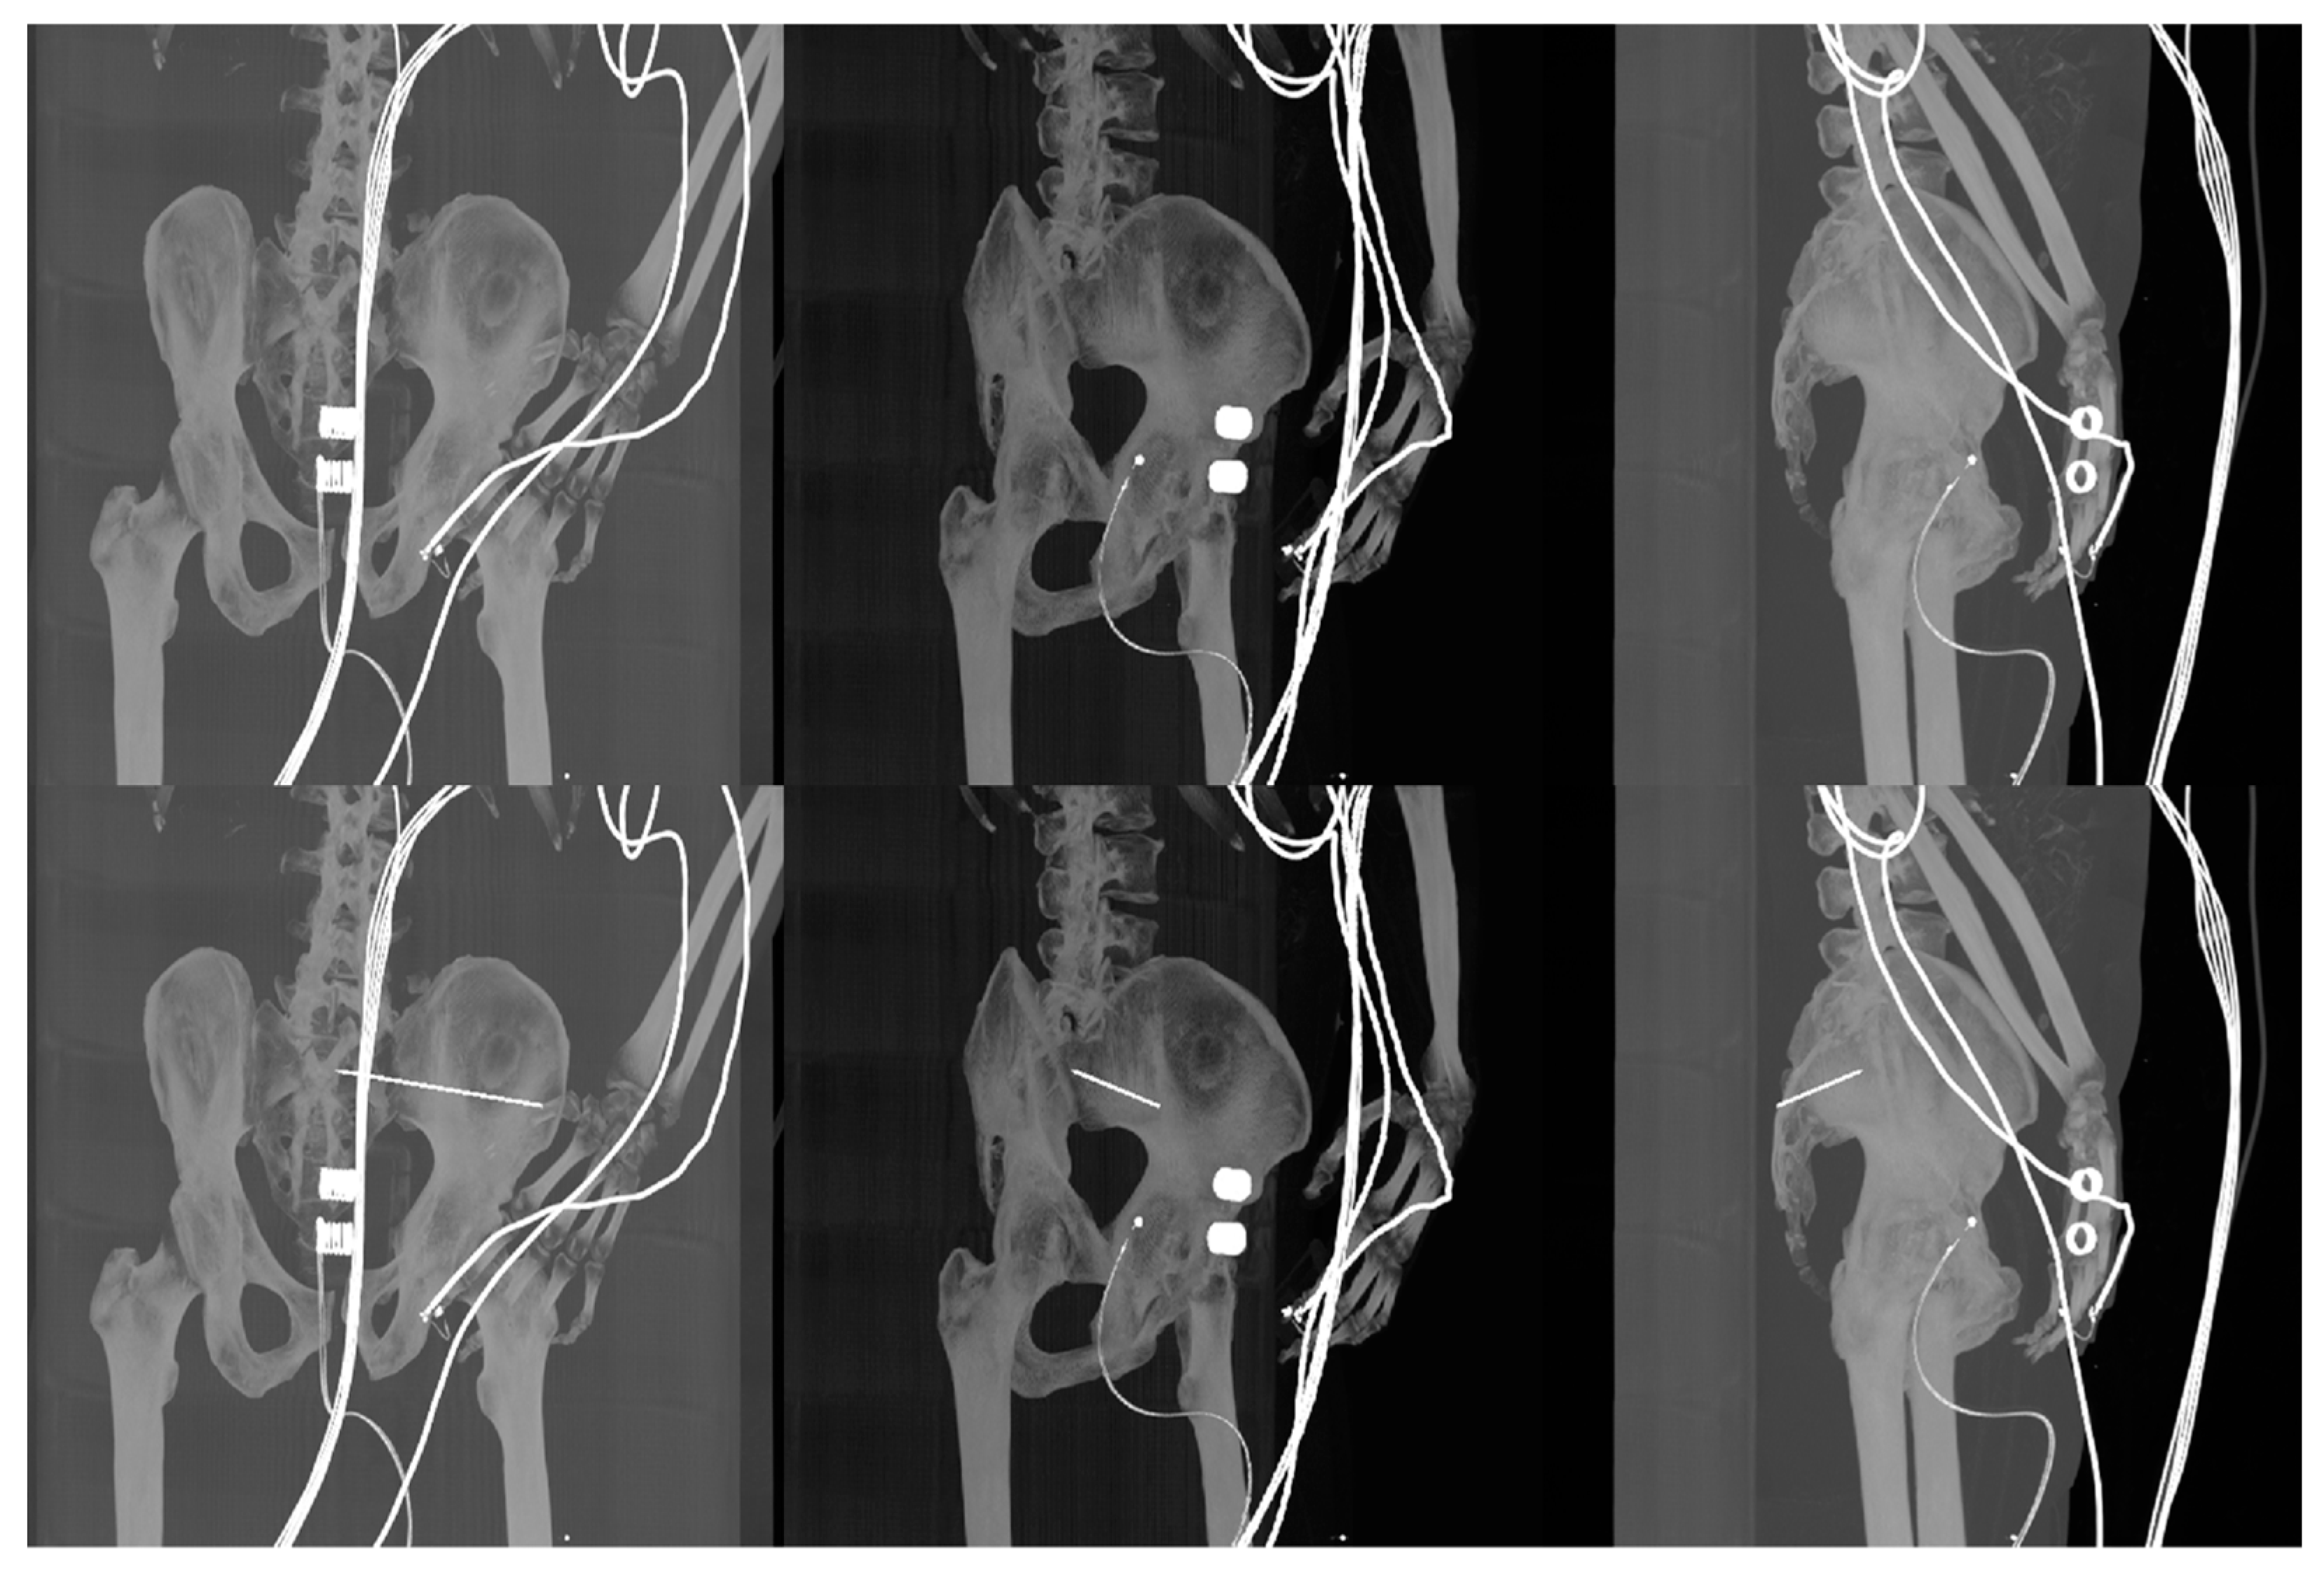

- Generation of digitally reconstructed radiograph (DRR) projections

- Multimodal image registration of DRR projections to a reference X-ray image